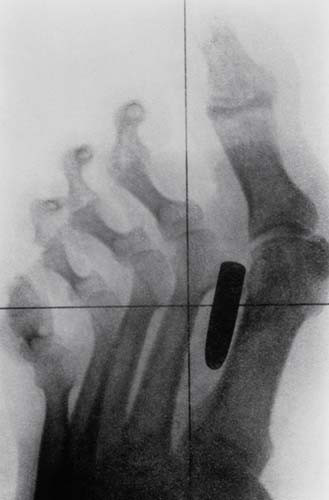

Bir erkeğin orta işaret parmağı ve orta parmak kemiklerine saplanmış bir çivi.

Bu röntgenler gerçek! - Resim: 3